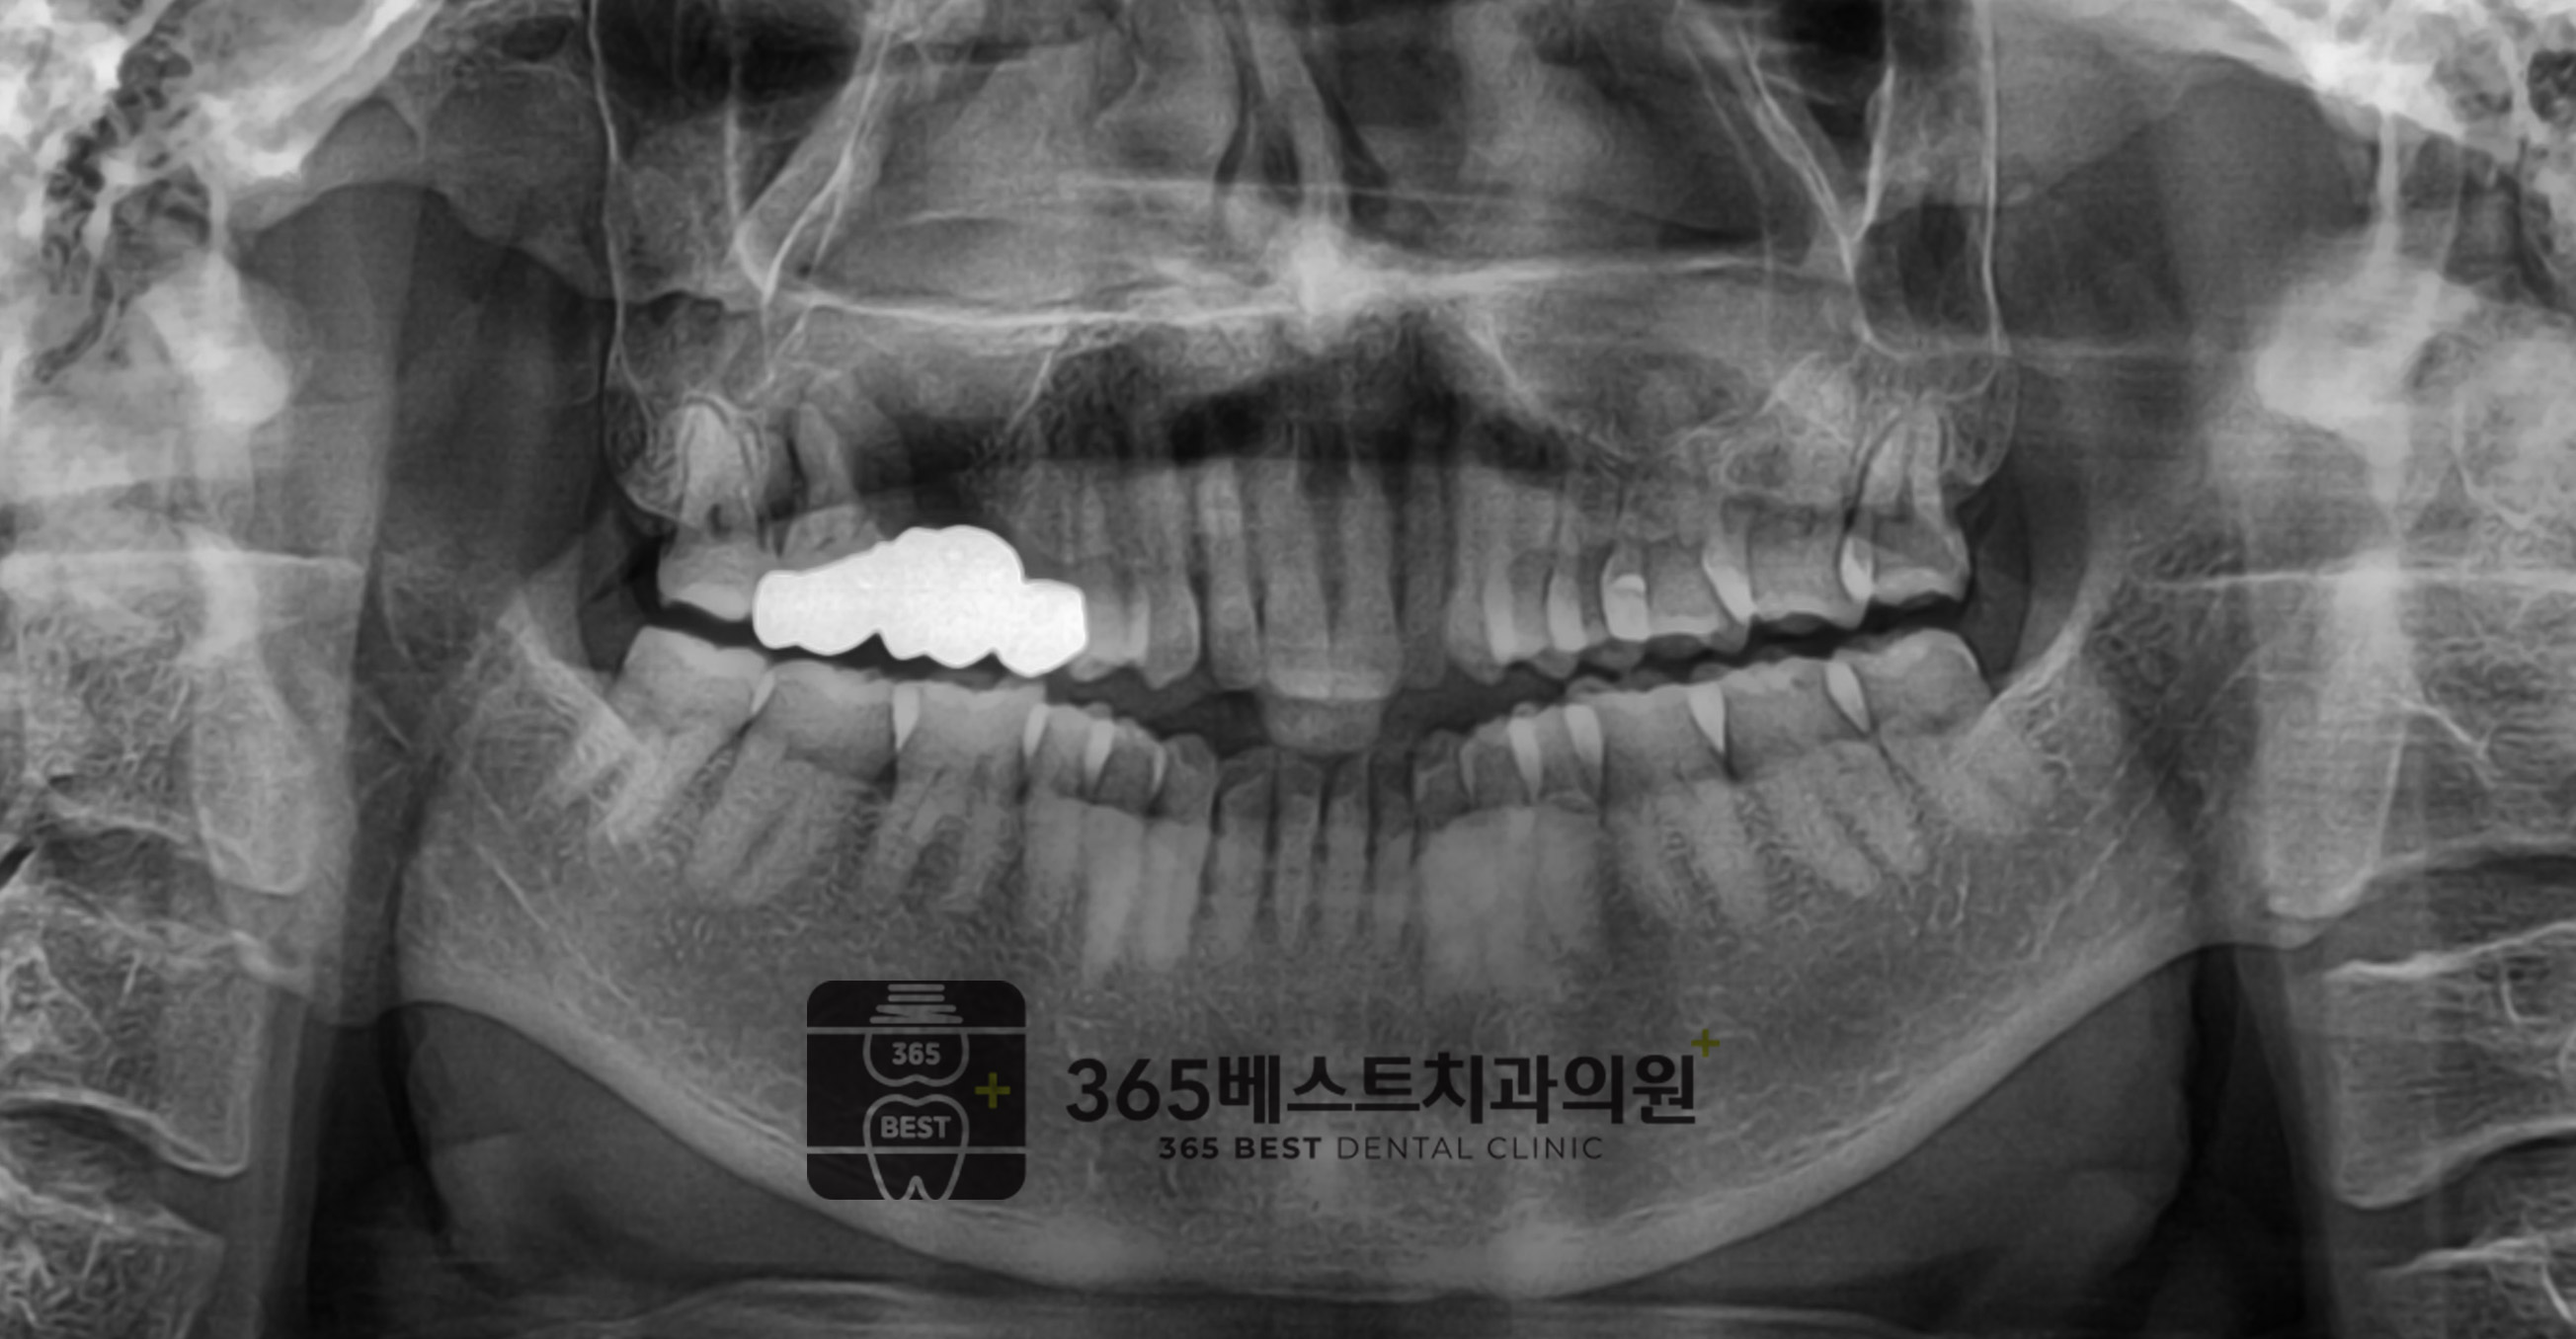

[임플란트]골재건

상악-구치부-2개-발치 후 골재건, 62세 남성

(후)